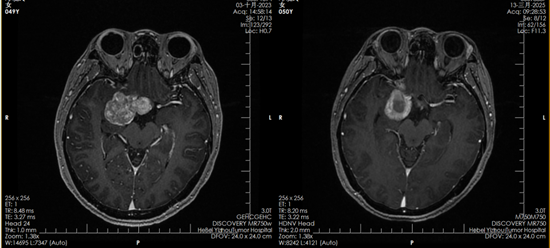

2023年10月,鄧女士正式開(kāi)始質(zhì)子治療。一個(gè)多月里,她接受了30次治療?!爸委煹臅r(shí)候一點(diǎn)感覺(jué)都沒(méi)有,就像躺下來(lái)休息一會(huì)兒。要不是看到復(fù)查影像里的腫瘤變化,我都不敢相信這是真的?!编嚺空f(shuō)。

質(zhì)子治療前后對(duì)比影像

如今,復(fù)查影像顯示腫瘤已被有效控制,她的堅(jiān)持終于換來(lái)了可喜的結(jié)果。